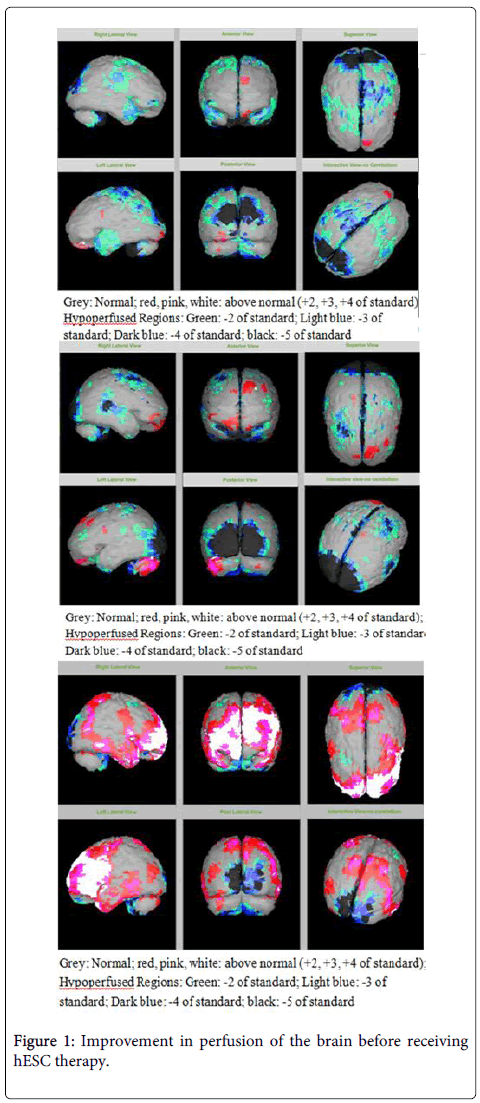

該患者的SPECT掃描如圖1和2所示。

SPECT掃描

在研究開始和結束時,23名患者接受了SPECT掃描。在枕葉或額葉或雙葉中觀察到灌注不足。23例接受SPECT掃描的患者中,5例患者表現為枕葉灌注不足,7例患者表現為額葉灌注不足,11例患者表現為枕葉和額葉灌注不足。

總體而言,治療結束時,2名患者的灌注正常,18名患者(12名男性和6名女性患者)顯示灌注顯著改善(>60%),3名患者顯示灌注中度改善(30-60%)。大多數在接受hESC治療前額葉和枕葉嚴重低灌注的患者在接受 hESC 治療后情況有所改善。23名可獲得SPECT掃描報告的患者的GMFCS評分在hESC治療后有所改善(表2)。

眾所周知,神經干細胞可以通過重新填充受損區域并防止細胞進一步退化來恢復正常視力。hESC通過增殖成相似的細胞類型來啟動受損細胞的再生。在本研究中觀察到灌注改善,這反映在SPECT掃描中。詹森等人研究顯示,一名5歲腦癱患者在接受臍帶血干細胞治療2個月后視力有所改善。